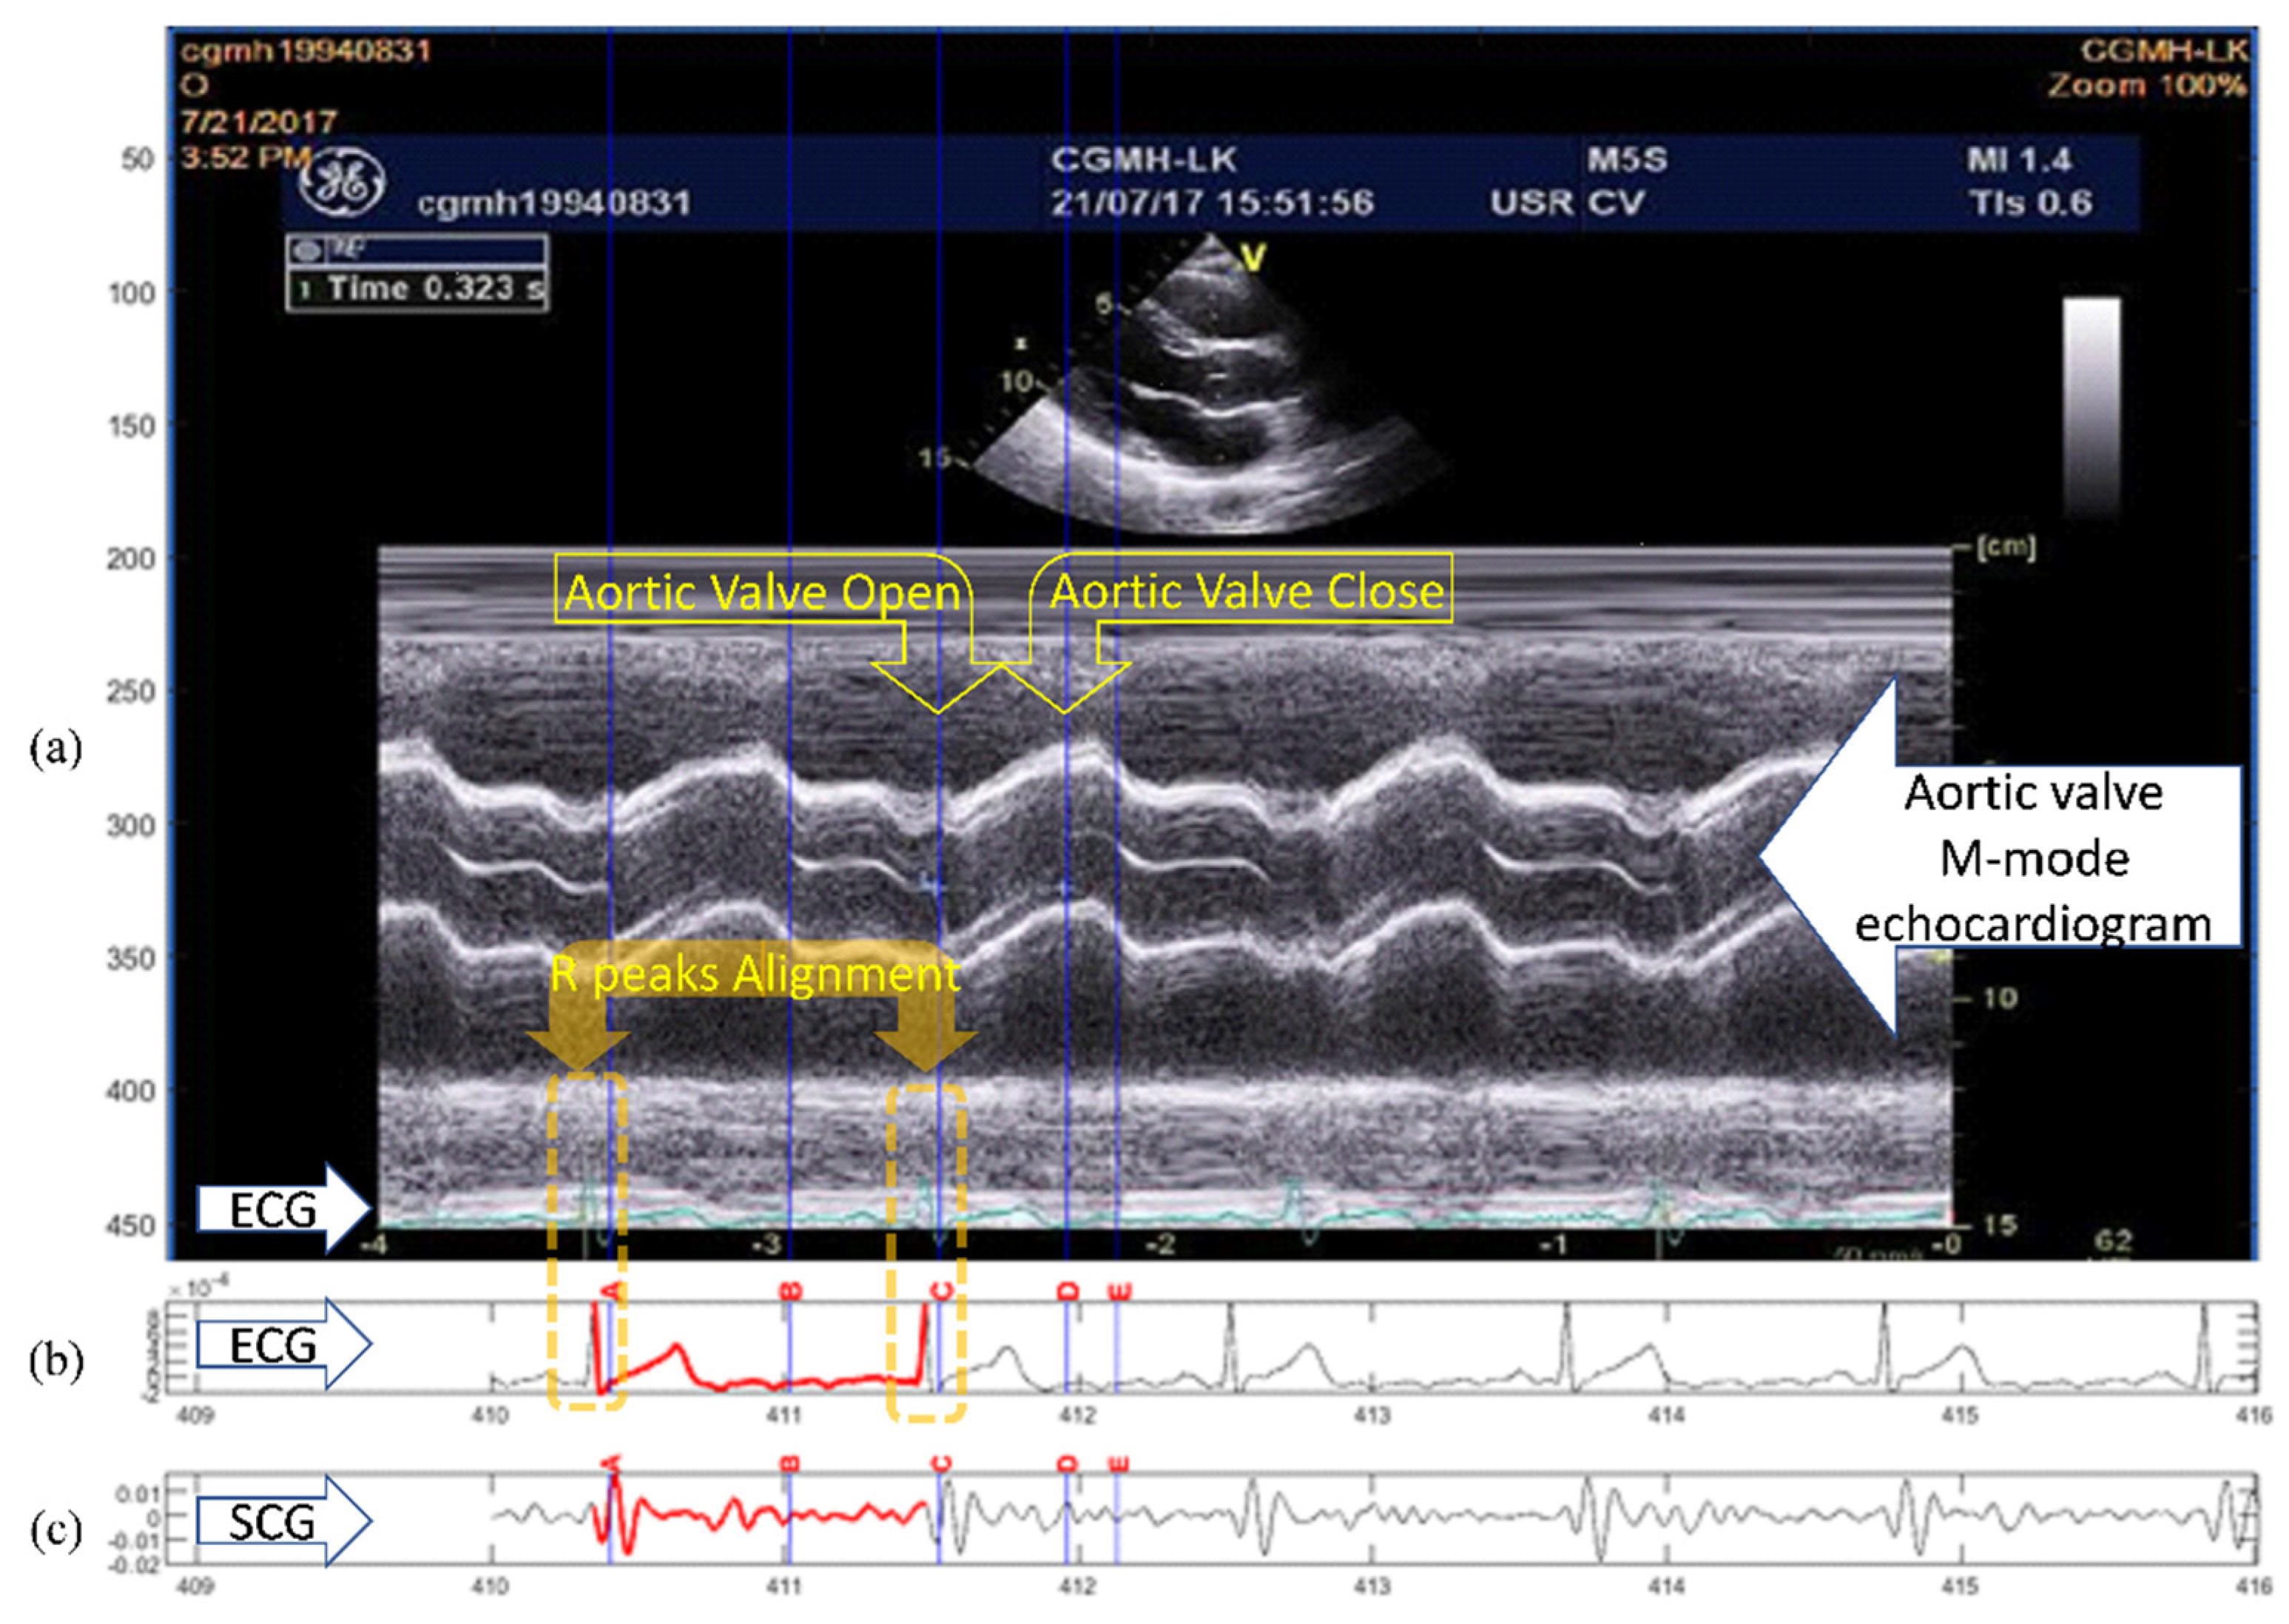

An example of the conventional quasi-synchronous alignment is displayed in Figure 1. The figure consists of an M-mode image of aortic valve motion (with synchronous ECG signal shown overlapped in the lower part of the image) (Figure 1a), an ECG (Figure 1b) and SCG (Figure 1c) signal pair measured at the same time. To align the echocardiogram image and the SCG signal quasi-synchronously, R peaks from the two ECG signals were employed as the beacon targets. The ECG signal in Figure 1b was rescaled and shifted to align the R peaks to the ECG R peaks of the echocardiogram image (in Figure 1a) as indicated in the orange boxes. The vertical blue lines in Figure 1 link the timing information between the echocardiogram image and SCG signals. As the events visually identified in the echocardiogram image, the timing positions of the fiducial points in SCG signal could be easily obtained. Therefore, the fiducial points of the SCG signals could be detected. This technique had also been applied to color Doppler echocardiogram and tissue Doppler echocardiogram images to identify six new fiducial points [9].

Figure 1. Example of the quasi-synchronous alignment for an echocardiogram image and an SCG measurement: (a) M-mode echocardiogram image of the aortic valve (with an ECG signal at the bottom of the image); (b) ECG signal simultaneously measured with SCG signal; (c) SCG signal.